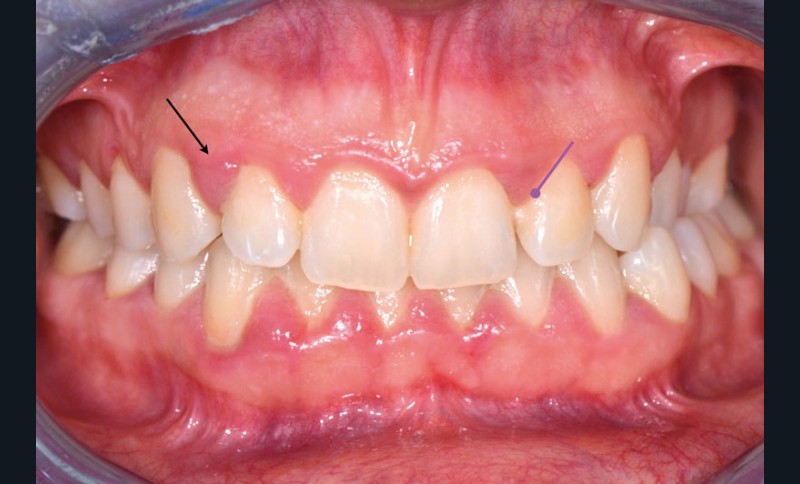

Elles s’identifient par une inflammation gingivale, caractérisée par une gencive rouge, voire violacée, œdématiée, qui saigne au brossage et/ou spontanément (fig. 1).

La spécificité des gingivites est l’absence de perte d’attache (ou de poches parodontales) et de destruction osseuse.